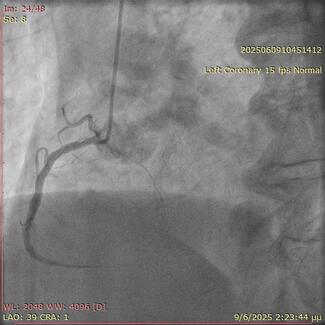

Oscar Lagos Degrande, MD; Carmen Lluch Requerey, MD; Miguel Angel Montilla, MD; Santiago Camacho Freire, PhD; Jessica Roa Garrido, MD; Elena Izaga, PhD; Antonio Gomez Menchero, MD

A 73-year-old man was hospitalized with acute coronary syndrome. Angiography showed severely calcified disease in the anterior descending artery and severe stenosis in the proximal, medial, and distal segments.